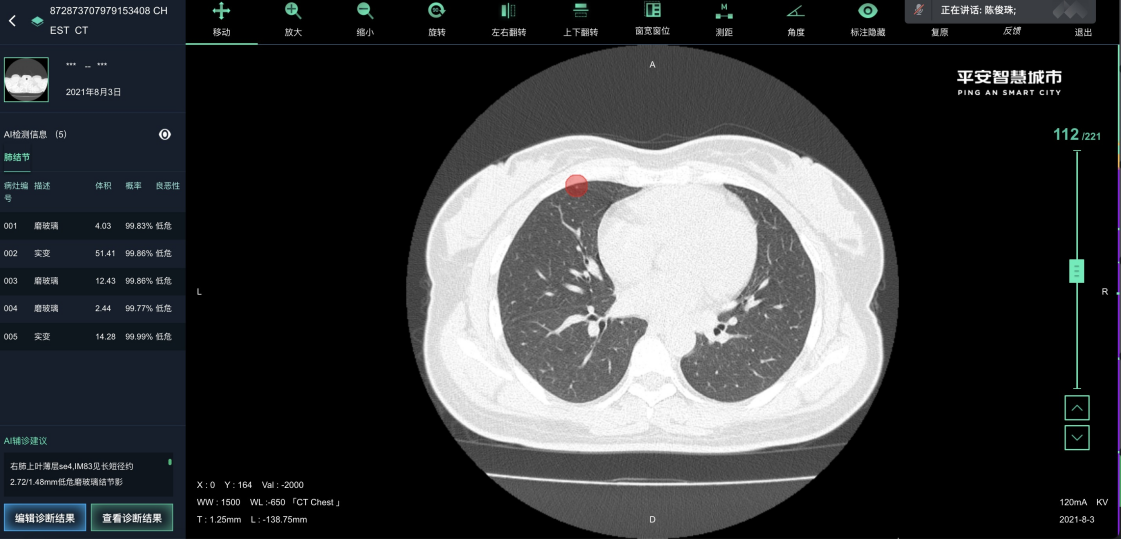

白云医疗影像系统是广州市白云区卫健委推动健全社区-中心医院体系的中间平台。白云医疗影像系统联合中心平台和各个社区医院实现患者影像检查的诊断和会诊功能。从中心平台可得到各个社区医院上传的患者影像数据进行诊断和联合会诊,并将诊断报告返回给中心平台。通过点击患者影像检查单中的AI影像分析按钮,可以跳转至AI影像分析系统上查看该患者的AI影像分析结果。普通影像分析和AI影像分析的结果可以大大地提高医生对患者病情诊断的准确率和效率,加强了各级社区医院与中心医院主治医生的交流与合作,均衡了各级医院医生资源,为广大患者带来更多便利。

为医疗影像提供了一种针对docom格式的图片文件的标注工具和存在方式。为不同医院的医生搭建远程会诊桥梁,实现AI阅片。